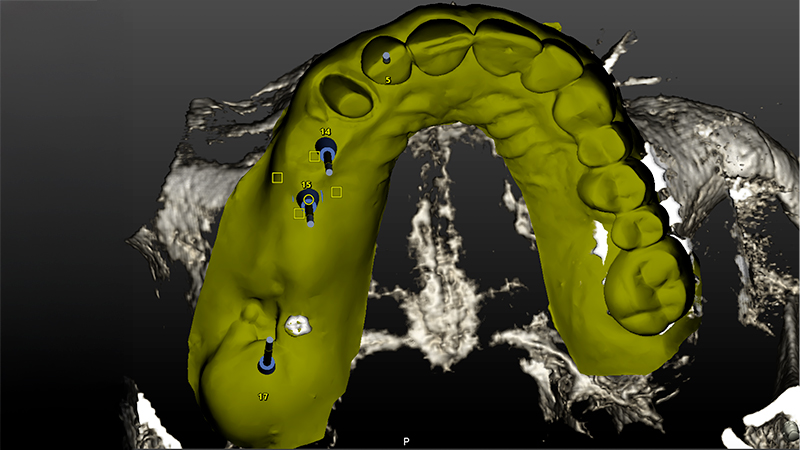

Veniva eseguita la pianificazione del caso con l'utilizzo dell'STL della Biocopia (Fig. 9) e della gengiva guarita (Fig. 10), e di tutti gli impianti: zona 12 con pianificazione post-estrattiva flapless con Socket Shield (Fig. 11), zona 14 (Fig. 12), zona 15 (Fig. 13) e zona pterigoidea (Fig. 14). Dopo la chirurgia (Video 1 e 2), OPT post-operatoria e endorali venivano fatte per valutare il rialzo di seno trans-crestale (Figs. 15, 16, 17, 18).

Pianificazione chirurgica della posizione implantare

Fig. 9 - Pianificazione chirurgica della posizione implantare su Software Navident (Claronav) basandosi sulla posizione dei denti originali mediante sovrapposizione di impronta ottica con e senza i denti (STL). Particolare attenzione è stata posta al parallelismo degli impianti 15 e 14, al corretto posizionamento con tecnica Socket Shield su 12 e alla correzione predefinita di 30° del moncone dell'impianto pterigoideo per mantenere il parallelismo conometrico protesico

Pianificazione chirurgica della posizione implantare su Software Navident

Fig. 10 - Pianificazione chirurgica della posizione implantare su Software Navident (Claronav) basandosi sulla posizione dei denti originali mediante sovrapposizione di impronta ottica con e senza i denti (STL). Particolare attenzione è stata posta al parallelismo degli impianti 15 e 14, al corretto posizionamento con tecnica Socket Shield su 12 e alla correzione predefinita di 30° del moncone dell'impianto pterigoideo per mantenere il parallelismo conometrico protesico

Fig. 11 - Pianificazione chirurgica della posizione implantare su Software Navident (Claronav) basandosi sulla posizione dei denti originali mediante sovrapposizione di impronta ottica con e senza i denti (STL). Particolare attenzione è stata posta al parallelismo degli impianti 15 e 14, al corretto posizionamento con tecnica Socket Shield su 12 e alla correzione predefinita di 30° del moncone dell'impianto pterigoideo per mantenere il parallelismo conometrico protesico

Fig. 12 - Pianificazione chirurgica della posizione implantare su Software Navident (Claronav) basandosi sulla posizione dei denti originali mediante sovrapposizione di impronta ottica con e senza i denti (STL). Particolare attenzione è stata posta al parallelismo degli impianti 15 e 14, al corretto posizionamento con tecnica Socket Shield su 12 e alla correzione predefinita di 30° del moncone dell'impianto pterigoideo per mantenere il parallelismo conometrico protesico

Fig. 13 - Pianificazione chirurgica della posizione implantare su Software Navident (Claronav) basandosi sulla posizione dei denti originali mediante sovrapposizione di impronta ottica con e senza i denti (STL). Particolare attenzione è stata posta al parallelismo degli impianti 15 e 14, al corretto posizionamento con tecnica Socket Shield su 12 e alla correzione predefinita di 30° del moncone dell'impianto pterigoideo per mantenere il parallelismo conometrico protesico

Fig. 14 - Pianificazione chirurgica della posizione implantare su Software Navident (Claronav) basandosi sulla posizione dei denti originali mediante sovrapposizione di impronta ottica con e senza i denti (STL). Particolare attenzione è stata posta al parallelismo degli impianti 15 e 14, al corretto posizionamento con tecnica Socket Shield su 12 e alla correzione predefinita di 30° del moncone dell'impianto pterigoideo per mantenere il parallelismo conometrico protesico